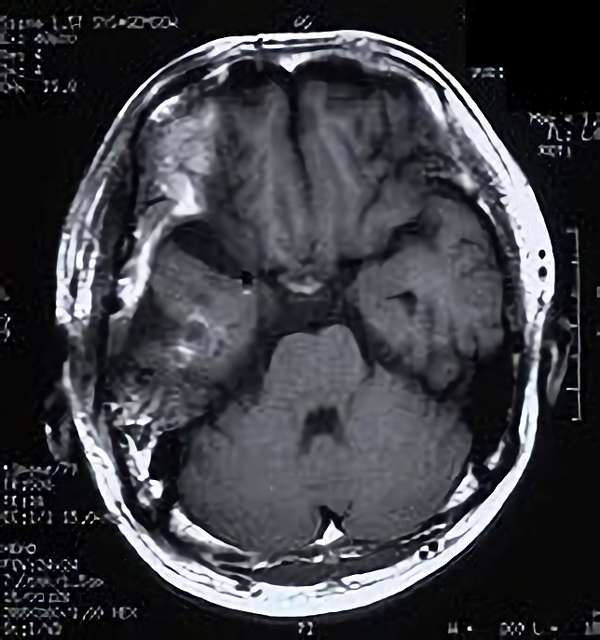

脳血管撮影

手術前

手術後